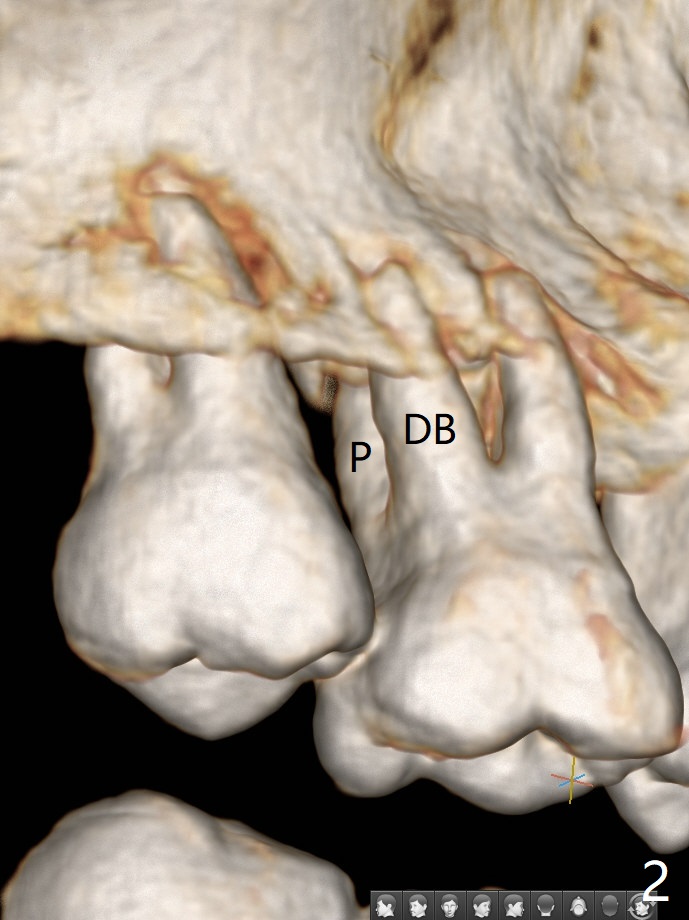

45岁女右上7严重骨质吸收终于开始出现症状(图一),虽然邻牙(6)骨质吸收也明显(图二,四,六,八,十),但是保留它,远中颊侧(DB),腭侧(P)根成为骨粉(图三,五,七,九,十一:红圆圈)支架。